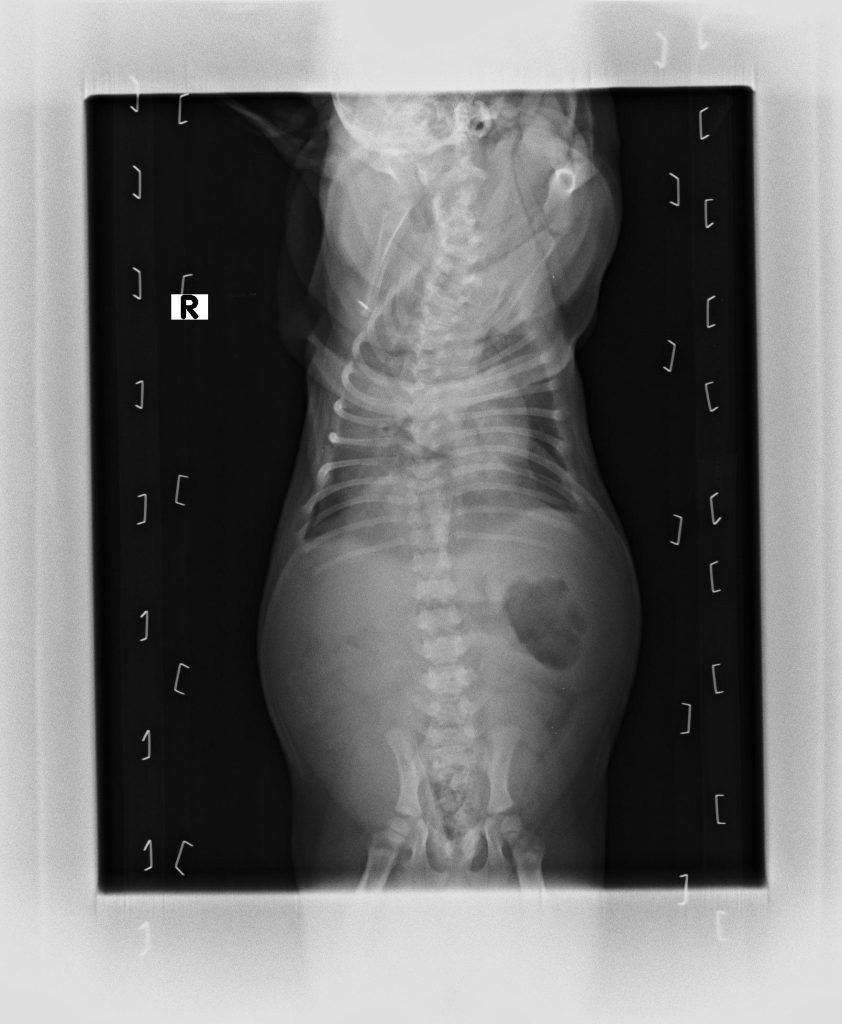

- X光檢查:檢視肺部、氣管、心臟大小